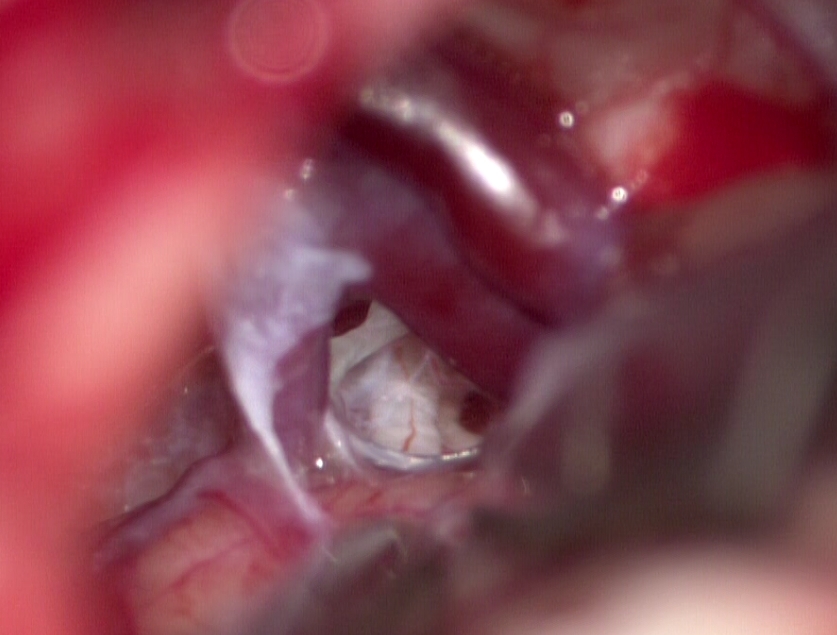

Пациентке сделали над небольшой разрез за ухом и просверлили отверстие размером меньше двух сантиметров, благодаря чему врач смог добраться к структурам мостомозжечкового угла под микроскопом. Хирург смог разъединить спайки, уложить специальный инертный материал и устранить компрессию. Любовь выписали через неделю после операции. Чтобы понять, насколько операция была эффективной, нужно время, но пациентке уже стало лучше.

Фото: Михаил Охлопков / vk.com